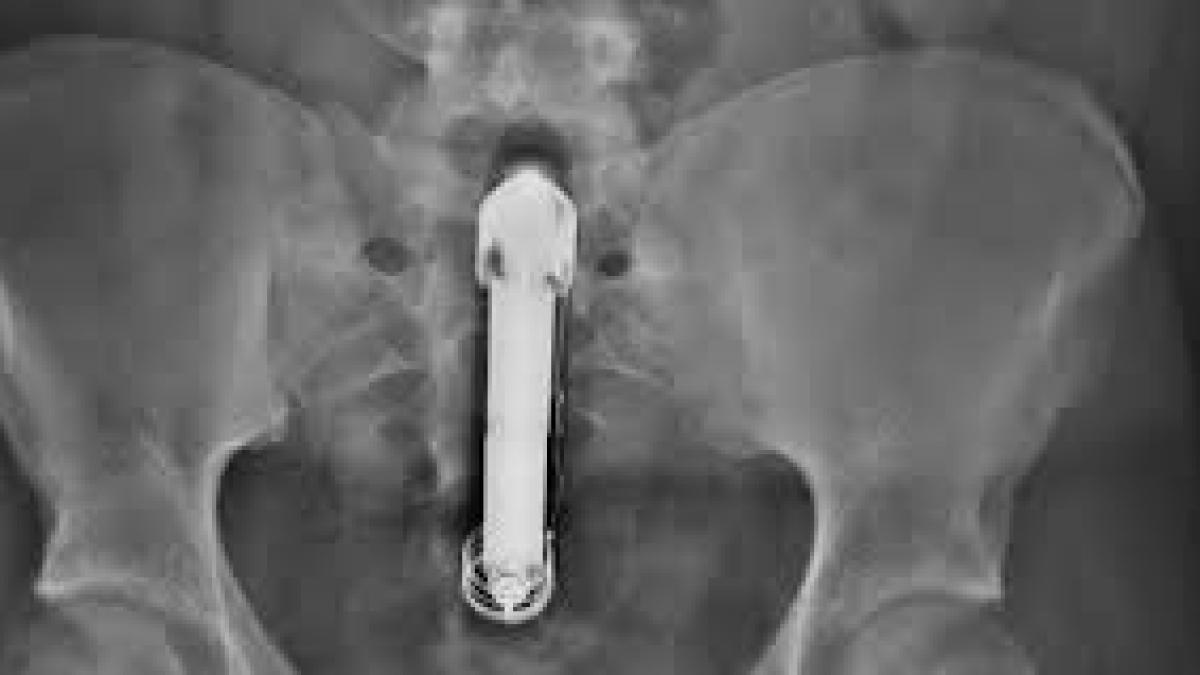

Jucărie sexuală, rămasă în vagin timp de 10 ani

O femeie de 38 de ani din Scoția, care suferea de incontinență urinară și de o pierdere drastică în greutate, a descoperit la un control medical că avea o jucărie sexuală blocată în vagin de zece ani.

Însă, deși își amintește momentul, nu mai știa ce se întâmplase și cu jucăria sexuală de 13 centimetri pe care o folosise atunci. Până la momentul descoperirii, obiectul sexual deja îi pusese viața în pericol, aceasta suferind de un blocaj al vezicii urinare care trimite urina înapoi în rinichi.